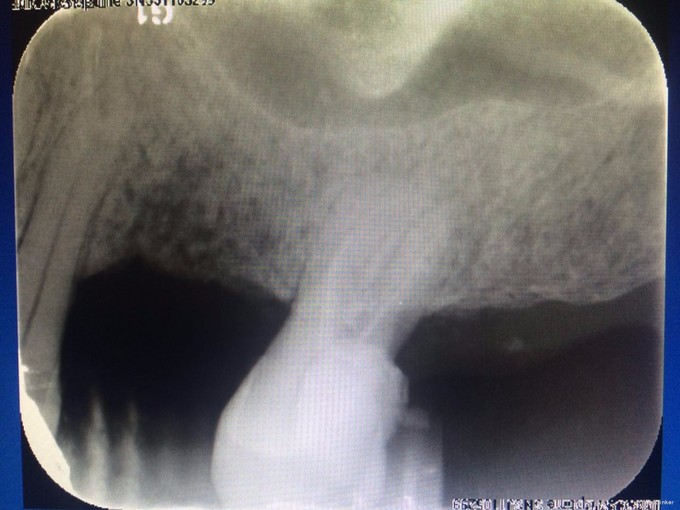

检查:#27 he 面见大量黑色腐质,叩(—),松(I),探(+),冷热测迟缓性疼痛,去除刺激后依旧持续一段时间,电测有活力,牙龈稍红肿,#26,#28已拔除,拔牙创愈合可。 X线示: #27根尖未见明显阴影,牙槽骨吸收至根中1/3

诊断:#27慢性牙髓炎 治疗: #27碧兰麻下开髓、揭全顶,寻找根管口,拔髓,次氯酸钠和双氧水交替超声冲洗,测量工作长度,根管预备,封Ca(OH)糊剂2两周,ZOE暂封。两周后复诊检查,患牙无叩痛,患者无不适,暂封存。去暂封,次氯酸钠和双氧水交替超声冲洗,再次测量工作长度,干燥,热牙胶充填。树脂充填治疗。